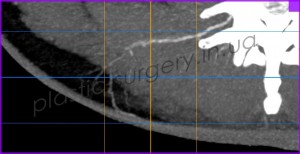

После предварительной локации точки выхода сосудов в покровные ткани в области поясницы, рядом с раневым дефектом с помощью аудио-допплера, больному было проведено более детальное обследование – КТ с ангиографией. При проведении исследования была визуализирована одна из люмбальных артерий и её перфорант справа от позвоночника, уточнено место выхода перфоранта, направление его оси и ветвление в покровных тканях (Рис. 3, 4, 5).

Рис. 5. Снимок компьютерной томографии с ангиографией. Визуализируется перфорант люмбальной артерии, направление его оси, ветвление артерии в покровных тканях.